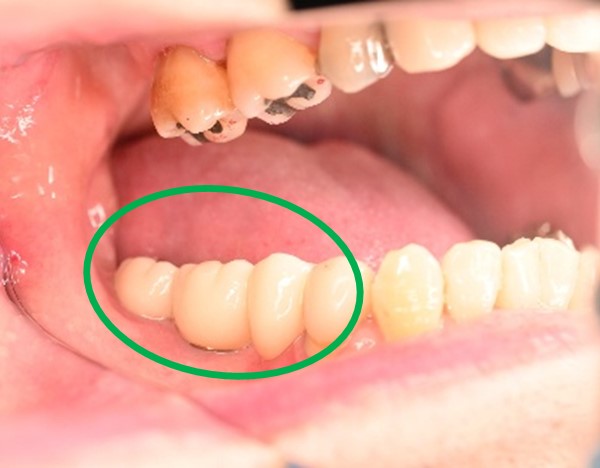

Before

抜歯後

After

右下のブリッジの支台になっている後方の歯が、歯根破折を起こしていましたので抜歯しました。インプラントを右下第一大臼歯部に1本埋入しました。

所感

右下のブリッジの支台になっている第二大臼歯が歯根破折を起こしていました。抜歯後欠損を補う方法には部分入れ歯かインプラントがあります。もし部分入れ歯を選択されていましたら、初めての入れ歯で自分の歯と同じ感覚で噛むことができないので、おそらく使わない入れ歯になっていたことが、想像できます。2本欠損でしたが、1本だけの埋入を希望されました。インプラントは、欠損を補う最良の方法と考えます。

インプラント1本:¥363,000(税込)